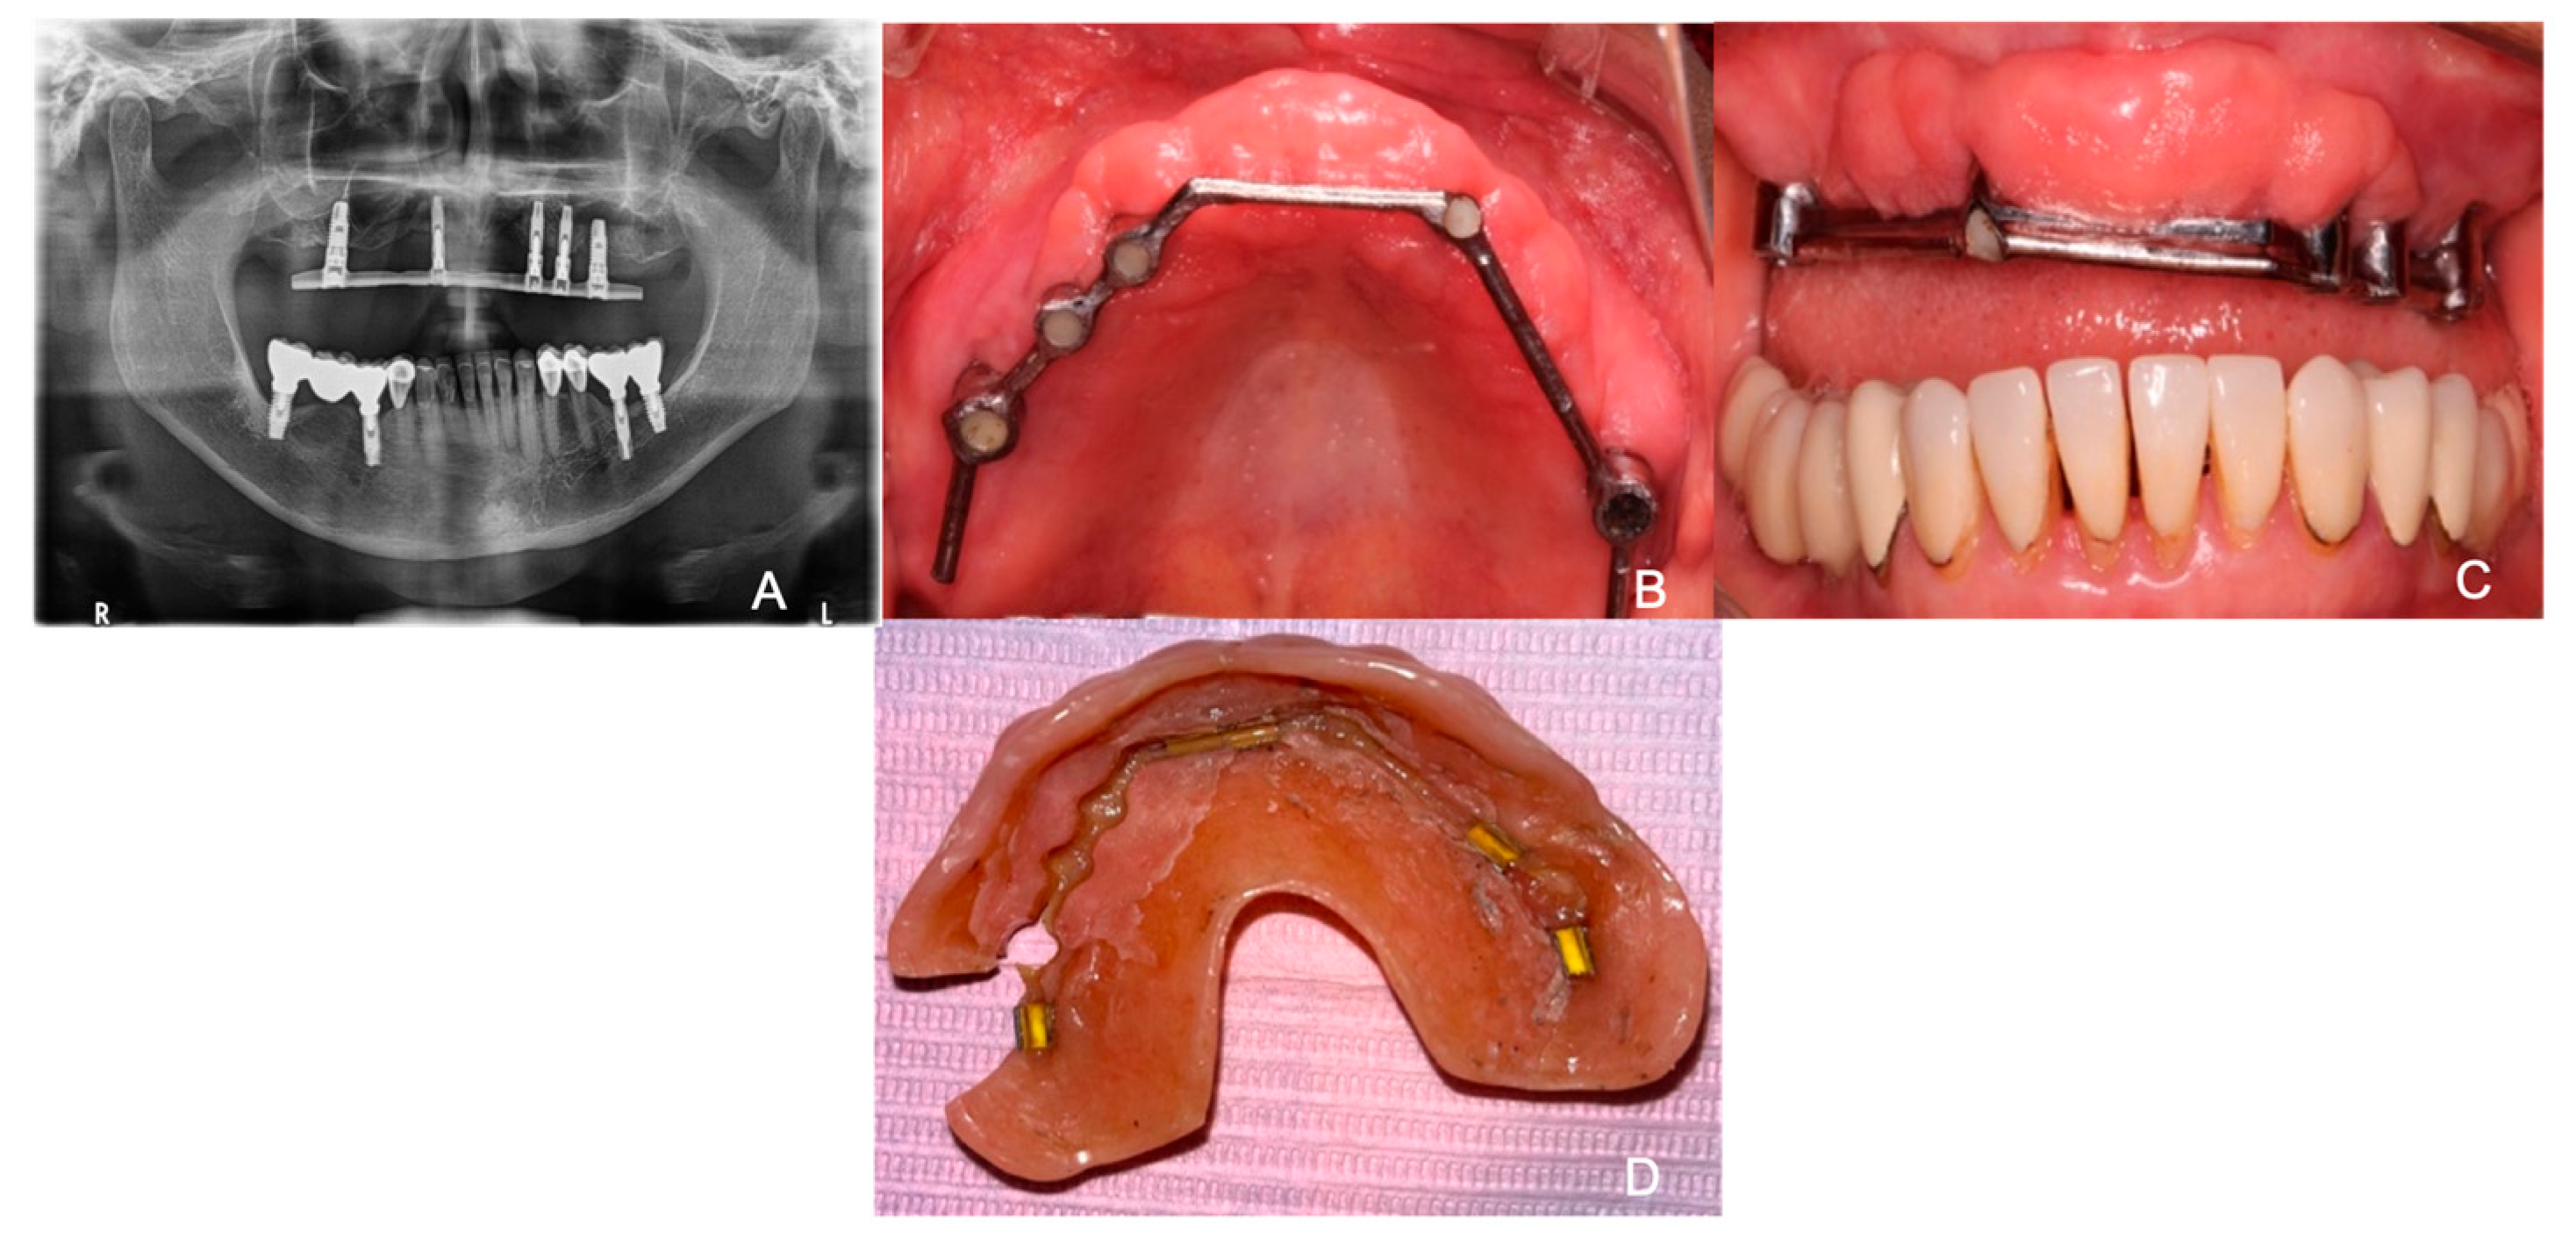

A 66-year-old female patient attended the diagnostic department with the primary concern being her fractured prosthesis and discomfort on the area where her provisional over-denture was placed. The patient reports being hypertensive and controlled type II diabetes. Additionally, it was noted that the patient had stomach ulcers and was a frequent smoker. The informed consent was obtained, and we filled in the medical history of the patient. A panoramic X-ray was performed for a first evaluation of the situation of the implants and the bar (Figure 1A). On intraoral examination, it was observed that there was the presence of white plaque on the bottom of the palate with a diameter of 5–6 mm, with defined edges and no increase in volume in which it would come off by scraping with gauze (Figure 1B). In addition, we observed a multinodular and oval-shaped lesion of 4–6 mm in diameter with well-defined borders in the anterior region of the maxilla on an erythematous background and semi-pedunculated base (Figure 1C). In the extra-oral examination, it was observed on the prosthesis that the bar-retained overdenture was fractured on the left posterior side along with whitish areas in the interior part of the overdenture that may have indicated plaque and fungal colonization (Figure 1D). Therefore, the patient was referred to the Oral Medicine, Periodontics, and Prosthodontics Department.

Figure 1.

(A) Panoramic radiographic image displaying the failed bar-retained attachment. (B) Bottom of the palate with white appearance and generalized inflammation. (C) Anterior part of maxilla with multinodular oval-shaped tissue. (D) Interior part of the overdenture with presence of plaque and a fracture in the posterior left side.